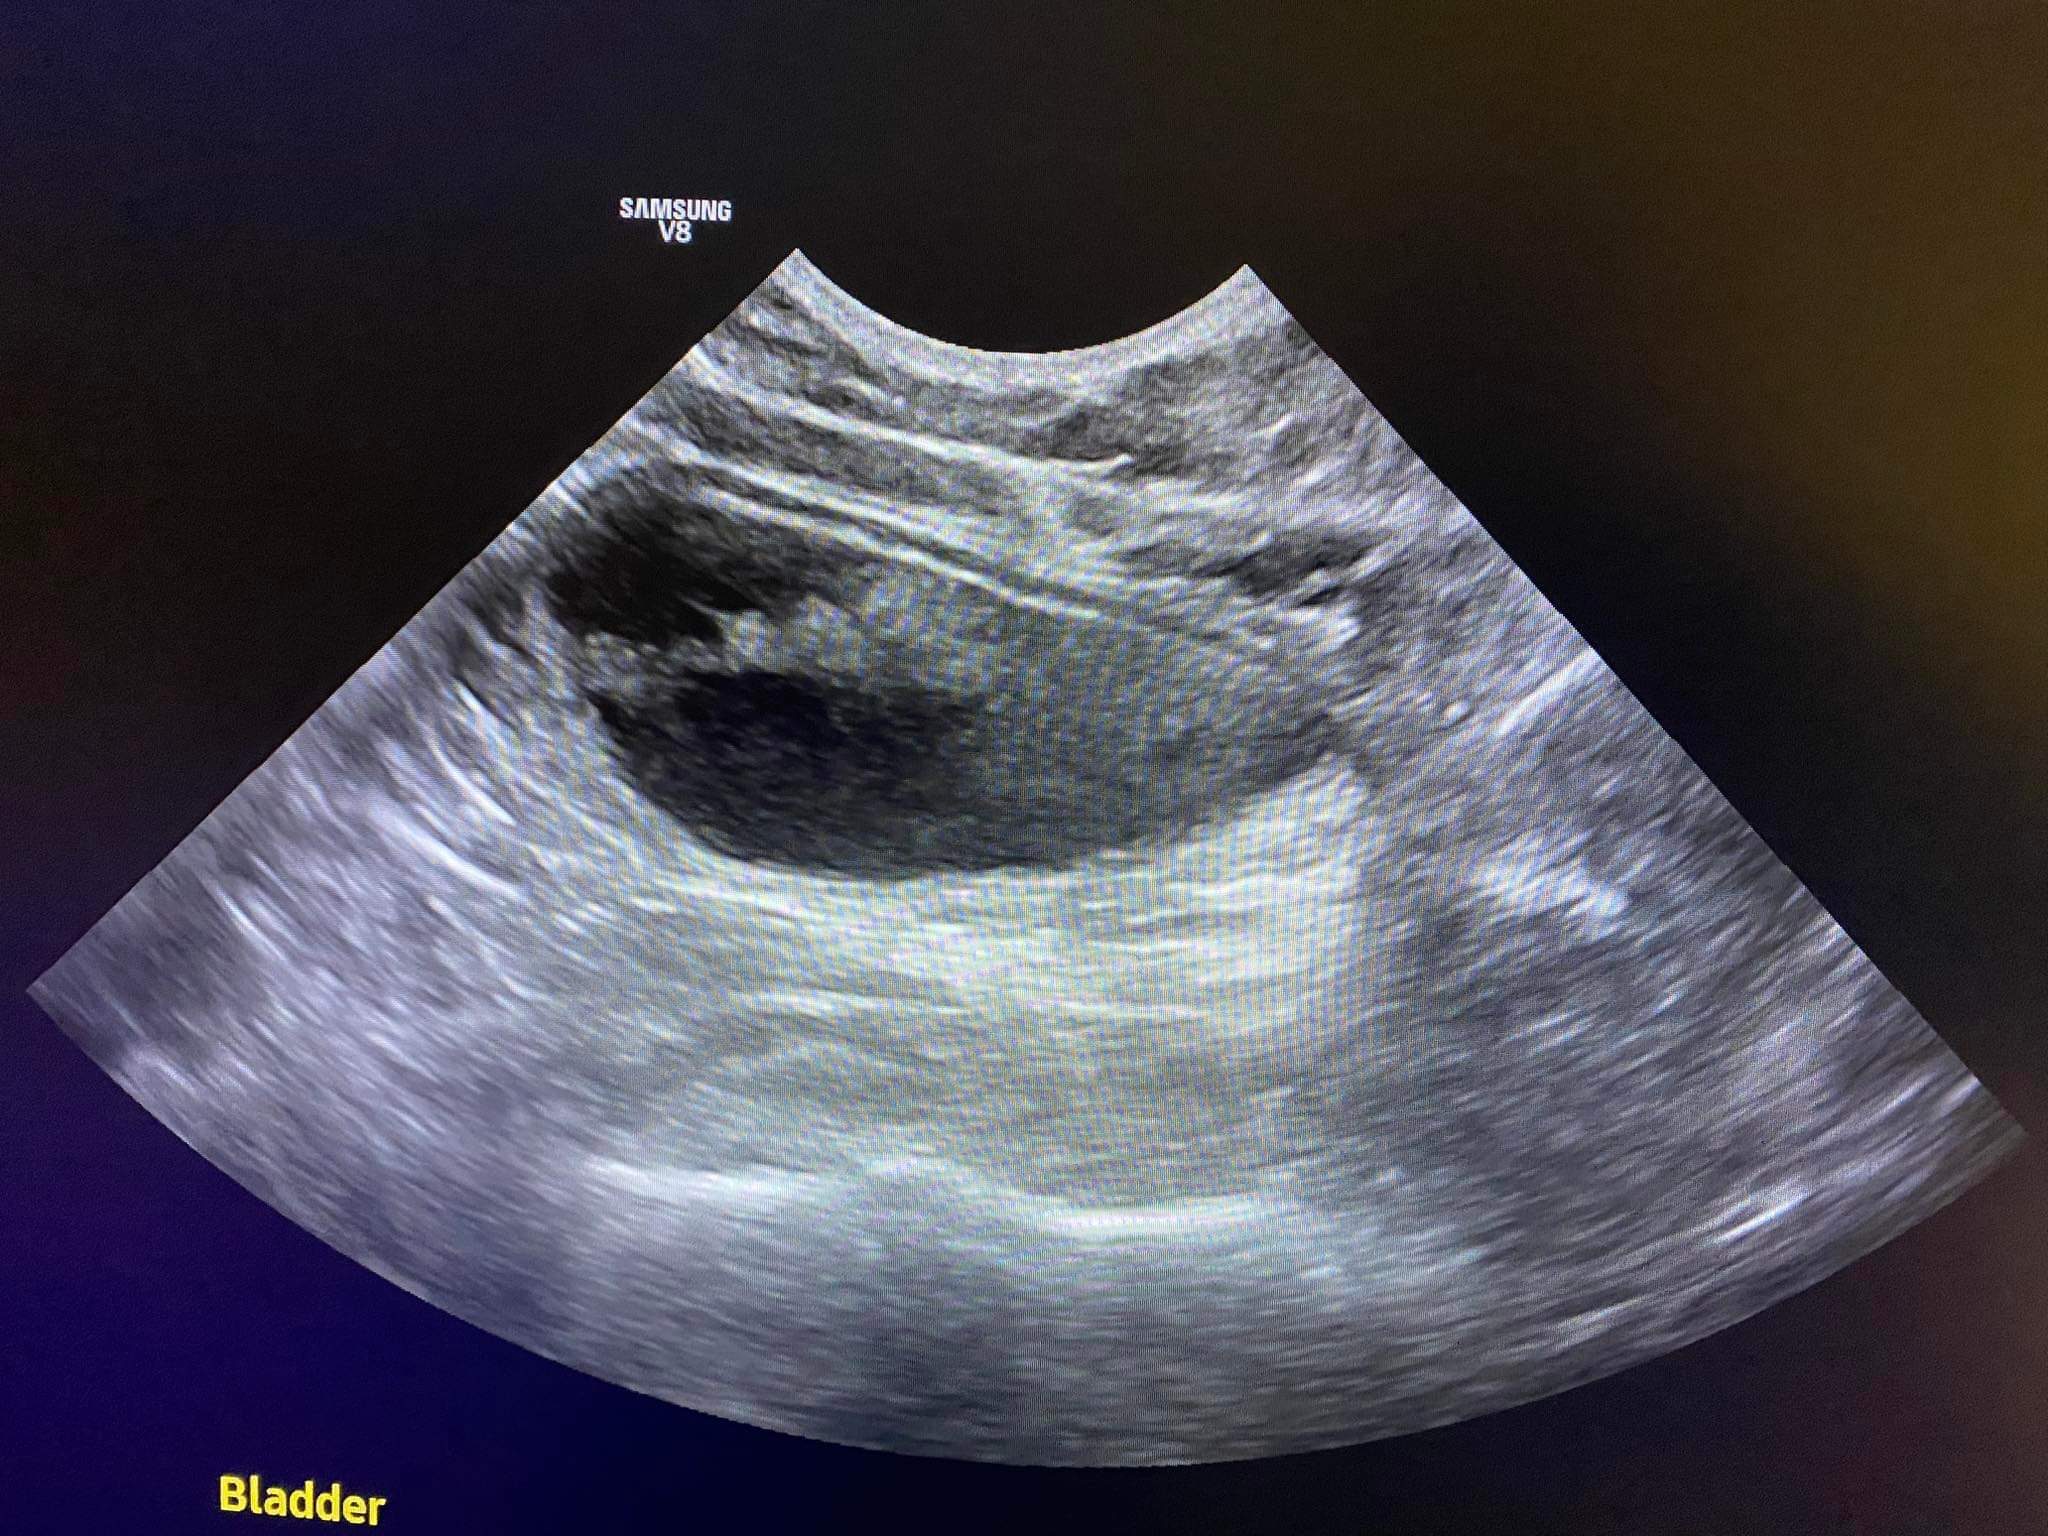

6.15kg

Bladder feel ok, his body feel much better than the other time

Checking u/s to see his latest bladder / organs conditions

Fpl negative

So if u/s still look ok, he can go back to void deck le – forgot the words totally too rush too tired I need to go work le. But means all good. Recover well.

His bladder is small today so can’t take urine test

Going to do an abdomen u/s to check on his inner issue.

140pm u/s results r out:

Bladder inside also look like got old blood clot.